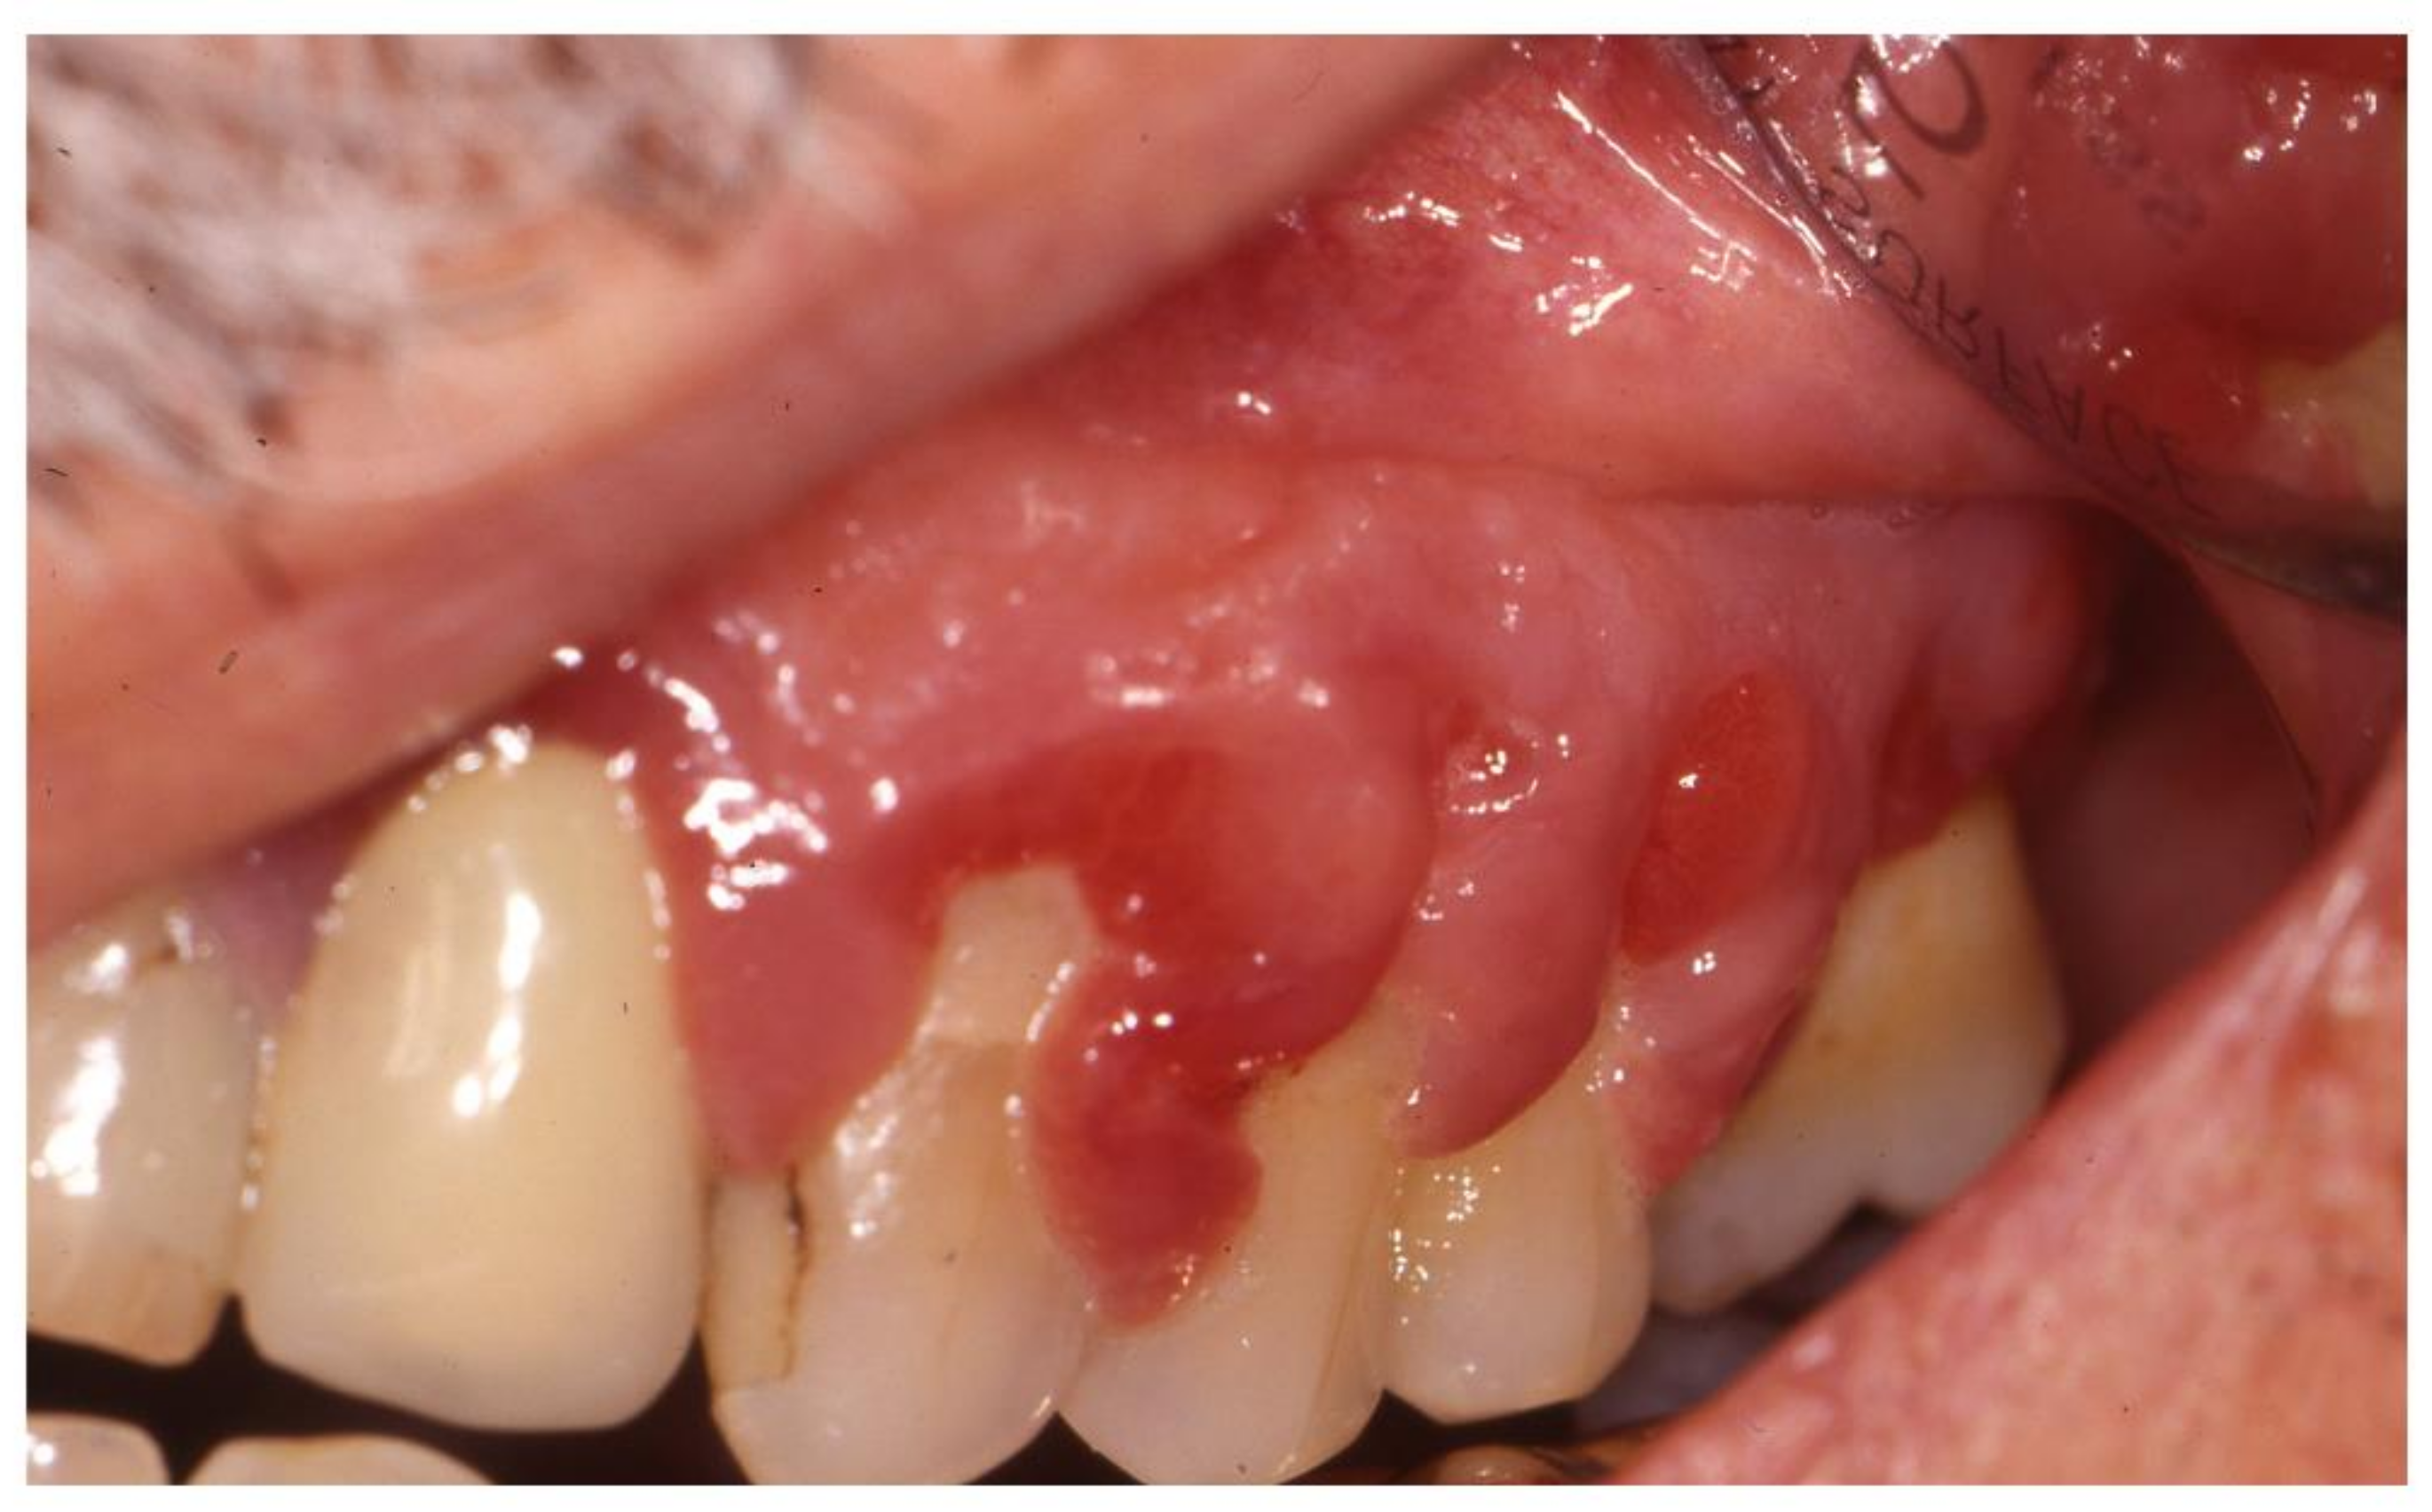

One typical form of gingival overgrowth is strawberry-like gingivitis, which is characterized by reddened, swollen and somewhat granular tissue that is often covered with petechiae and small punctate lesions. It is an almost pathognomonic oral manifestation of granulomatosis with polyangiitis (once known as Wegener’s granulomatosis) [27,28], whose typical presentation has recently been described by Ghiasi [27]. It is a very rare necrotizing granulomatous vasculitis (estimated incidence 9.8 per million per year) [78] that typically affects small and medium-sized vessels. The most frequently involved site is upper respiratory tract, which is involved in 90% of cases at diagnosis and is characterized by granulomatous sinusitis resistant to the standard sinusitis treatment regimens. Early referral to an otorhinolaryngologist and rheumatologist is essential because, if left untreated, it may lead to the progressive destruction of maxillary and mandibular bone and nasal cartilage, nasal septum perforation, saddle nose deformity, damage to the walls of the sinus and orbit, and fistula formation. Furthermore, granulomatosis with polyangiitis may have life-threatening complications such as lung and renal involvement, with the former being typically characterized by alveolar hemorrhage, and the latter by necrotizing glomerulonephritis [79]. Other oral manifestations include mucosal ulceration with non-specific histology findings, and lingual necrosis, which has also been reported as a rare presenting sign [80]. Anti-neutrophil cytoplasm antibodies (ANCAs) are present in 90% of patients, particularly with the cytoplasmic fluorescence pattern of anti-PR3-ANCA [79]. The mainstay of the treatment of granulomatosis with polyangiitis is a combination of glucocorticoids and cyclophosphamide to induce remission, followed by maintenance treatment with azathioprine and methotrexate [79]. Rituximab has recently been approved for the induction and maintenance treatment of ANCA-associated vasculitides [81,82].

The differential diagnosis of gingival overgrowth includes hematological malignancies, granulomatous diseases, genetic disorders and drug-induced gingival overgrowth [77]. Gingival infiltration may be the first clinical manifestation of leukemia, and has been described in more than 60% of cases of acute monocytic leukemia and about 20% of cases of acute myelomonocytic leukemia [83]. Possible causes of granulomatous lesions include sarcoidosis, Crohn’s disease and tuberculosis, whereas the most frequent genetic disorder causing gingival overgrowth is hereditary gingival fibromatosis [77]. Drug-induced overgrowth should be considered in IRD patients taking antiepileptic drugs, calcium-channel blockers, and cyclosporine A (Figure 5) [77], and patients should be informed of this possible side effect, which usually resolves after a dose reduction or drug discontinuation. Switching to alternative drugs can also be considered: For example, tacrolimus is associated with a lower incidence and later onset of less severe gingival overgrowth than cyclosporine A [84].

Figure 5.

Gingival overgrowth caused by cyclosporine in a patient with psoriatic arthritis.